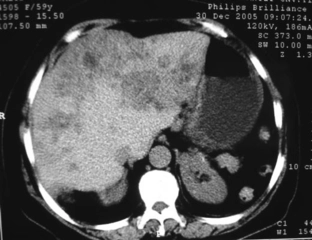

Tanı YöntemleriKafa içindeki lezyonların tanısı, genellikle hem klinik muayene hem de görüntüleme yöntemleri ile konulur. Kullanılan başlıca yöntemler şunlardır: